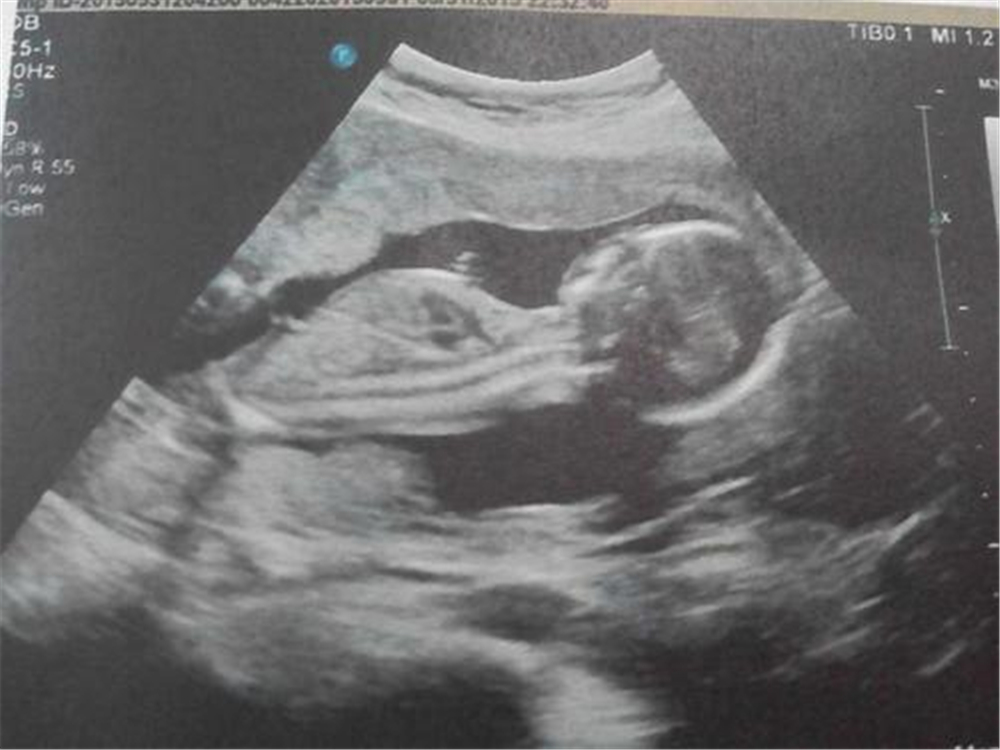

怀孕六个月时,小菊前往医院拍四维彩超,原以为检查过程也会像之前一样顺利,可是这一次,任凭门外的其他病人如何焦急医生都充耳不闻,仍仔细看着机器上显示的影像。

原来,医生从影像上看出宝宝的手部有不正常的阴影,怀疑是有畸形。但手指部位本来就不在排畸项目检查中,小细节上影像不清,目前只能确定存在畸形,具体情况未知 。